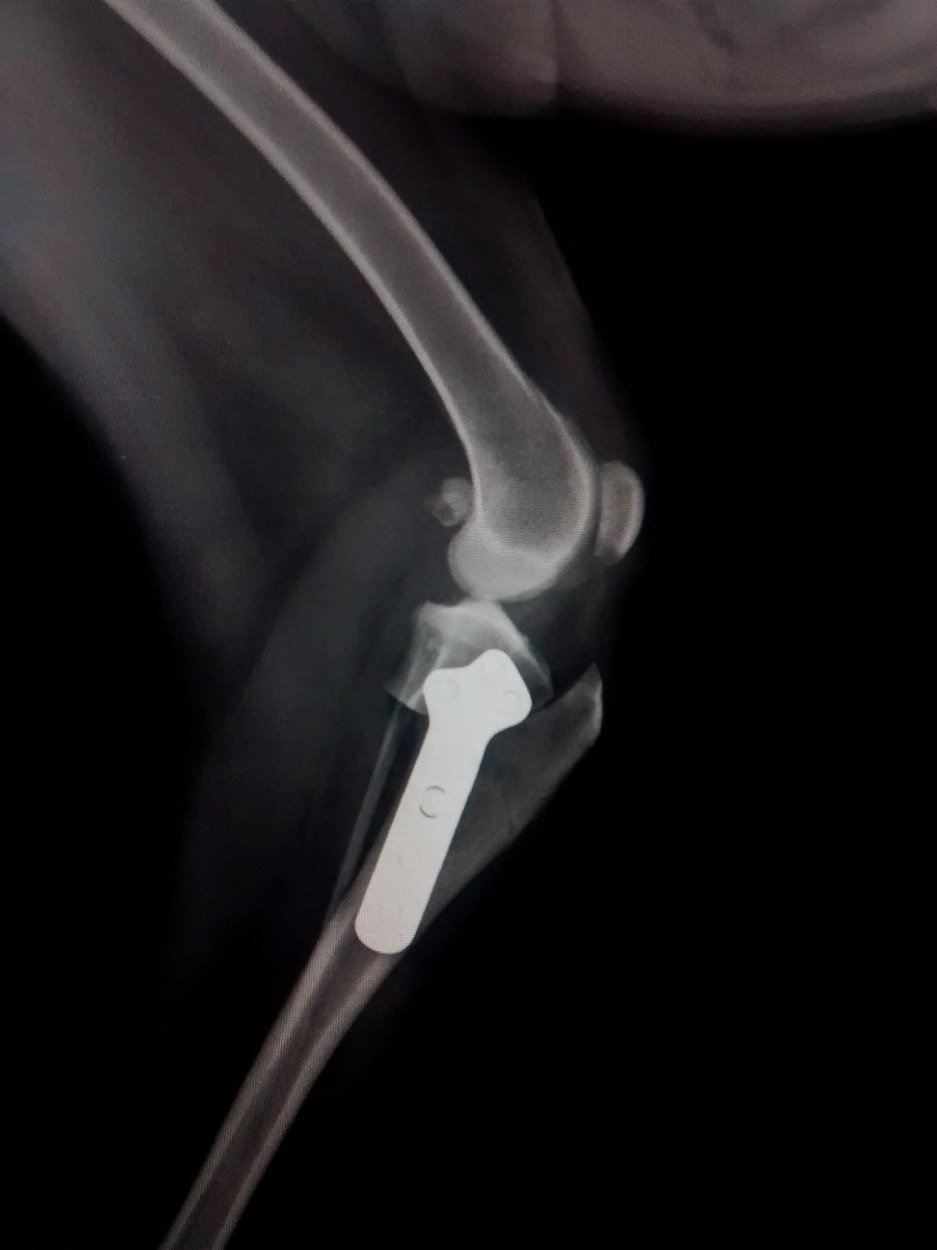

A Ruptura de ligamento cruzado cranial (RLCcr) é uma afecção muito comum nos cães, este caso refere-se a um cão macho mancando de forma aguda que ao exame foi feito o diagnostico de RLCcr. Optou-se por sua correção cirúrgica utilizando a ténica de TPLO, mundialmente conhecida pela sua alta eficácia.